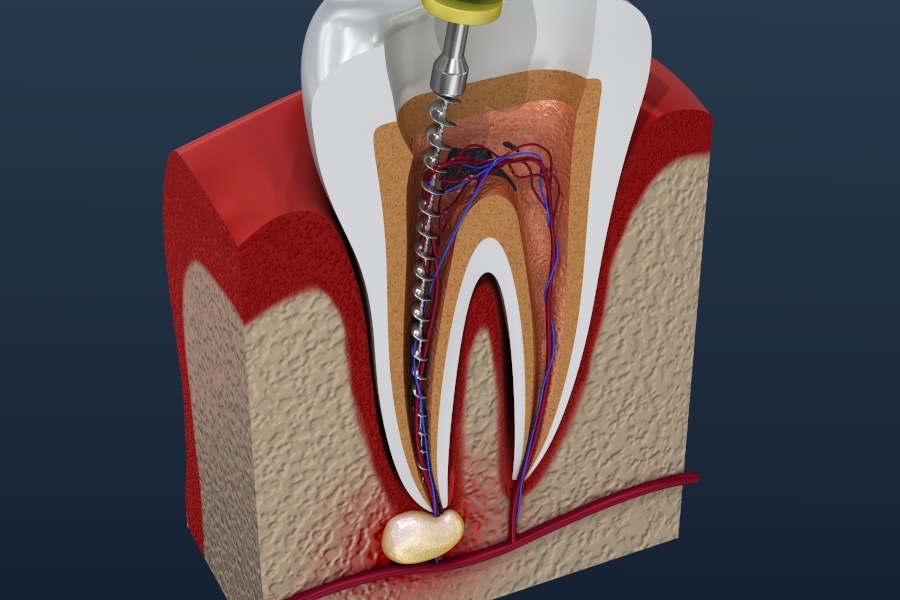

A root canal treatment is a dental procedure used to treat infection or damage inside the tooth, particularly in the pulp (the soft tissue inside the tooth containing nerves and blood vessels). When the pulp becomes infected or inflamed due to deep decay, cracks, or injury, a root canal is needed to save the tooth and prevent further damage

A root canal treatment (also known as endodontic therapy) is a dental procedure used to treat infection or damage in the pulp of a tooth. The pulp is the soft tissue inside the tooth that contains nerves and blood vessels. When the pulp becomes infected or inflamed due to decay, injury, or infection, a root canal can help save the tooth and prevent further damage.